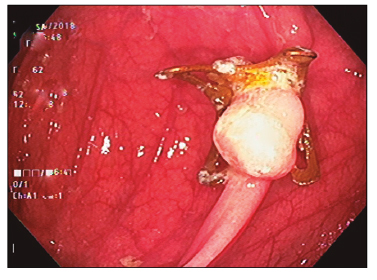

Se le realizó un nuevo intento de tratamiento endoscópico a los 4 meses con el objetivo de evitar una cirugía. La falta de elevación de la mucosa por fibrosis en un extremo fue un criterio de irresecabilidad para técnicas convencionales, motivo por el cual se procedió a la EFTR (Figuras 3 C y 4).

El clip cerró el sitio de la resección de manera eficiente, pudiéndose observar del lado intraluminal los bordes del peritoneo sujetos (Figura 5 A).